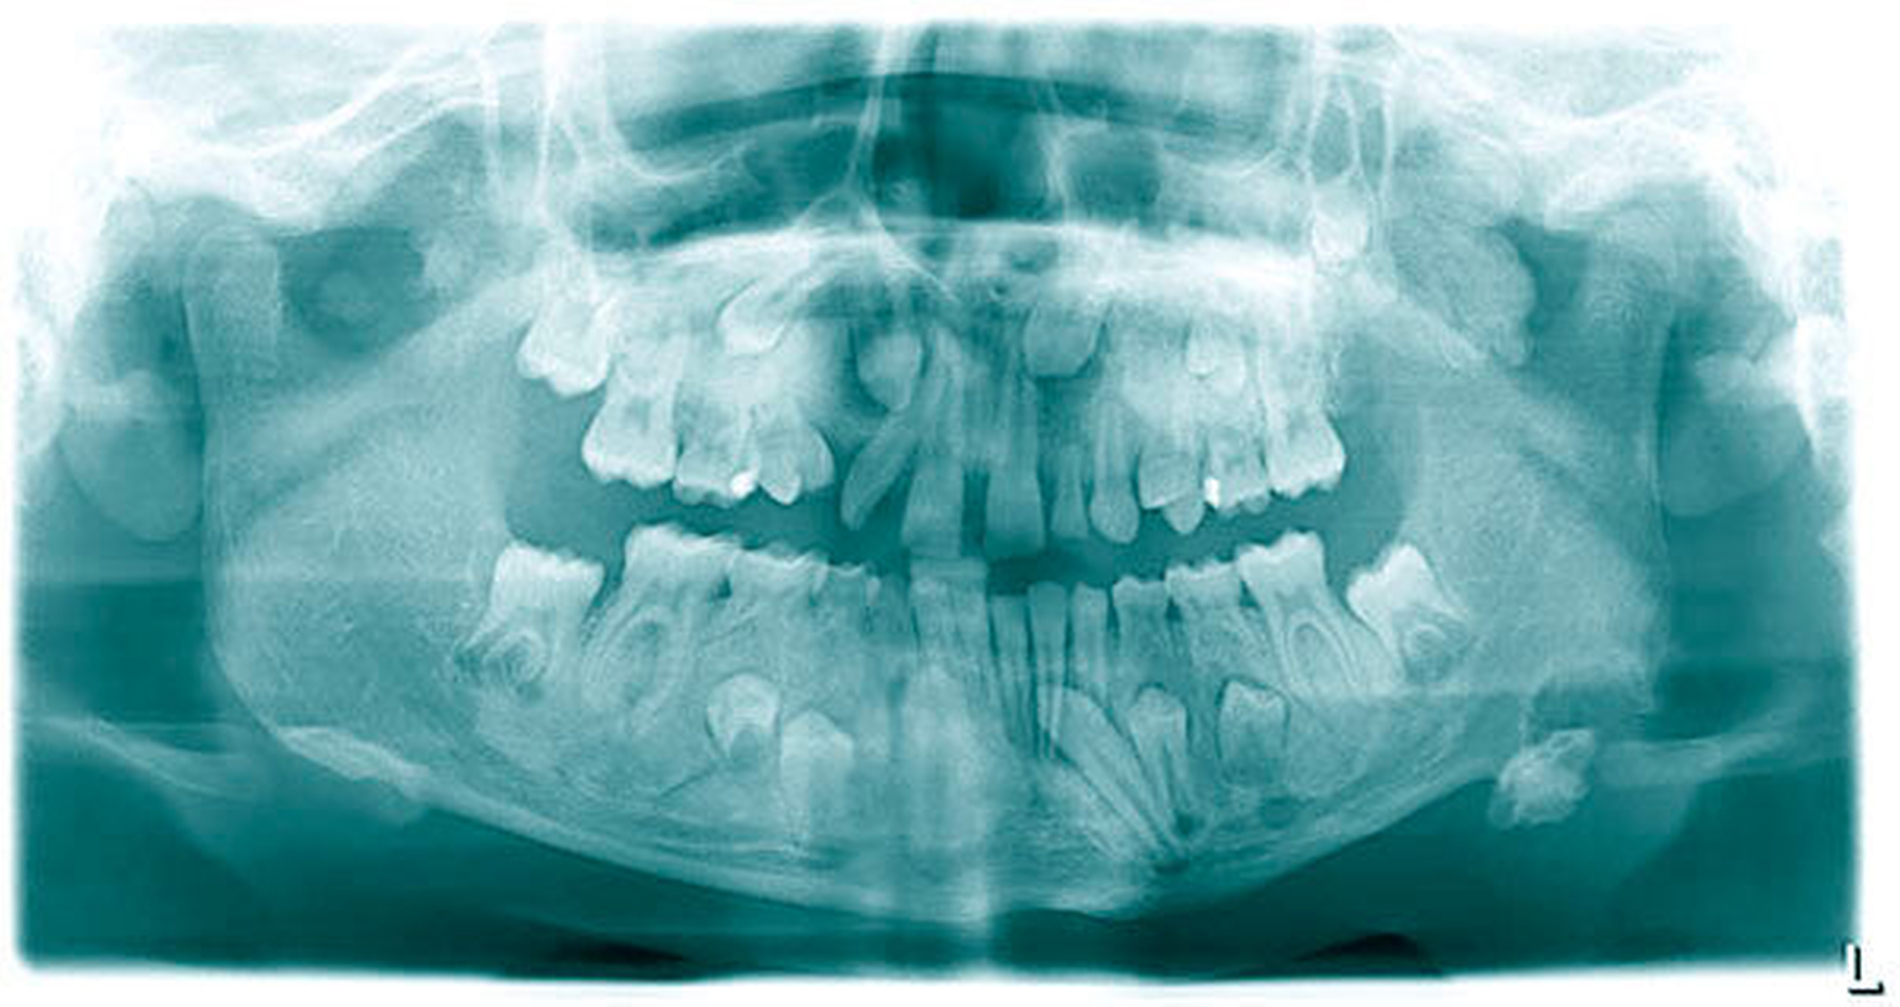

Die durchgeführte Panoramaschichtaufnahme zeigte eine knöcherne Apposition im Bereich des Kieferwinkels links basal mit einer Ausdehnung von 2 cm x 2 cm. Es bestand eine Retention der Zähne 15, 13, 23, 25, 27, 35, 34, 33, 43, 44 und 45 sowie die Nichtanlage des Zahns 22. Die Milchzähne 55, 52, 63, 65, 73 und 83 persistierten. Radiologisch zeigten Maxilla und Mandibula milchglasartige Strukturauffälligkeiten (Abbildung 2).